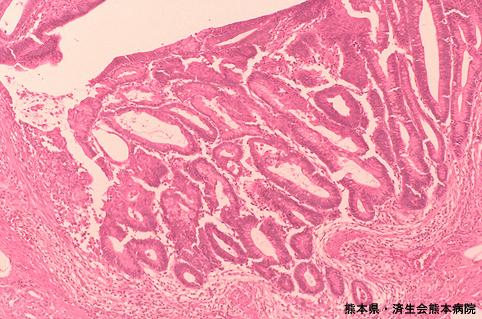

症例提示(所在地,施設名等): 熊本県・ 済生会熊本病院 (Dr. 吉田)

強拡では高分化型腺癌の像でした。

疾患(病理主体)の分類悪性上皮性腫瘍/腺癌

部位(臓器別)大腸/横行

検査方法ミクロ

腫瘍の肉眼分類0型(表在型)/IIa型(IIa+IIc)

病変の最大径(ミリ)20〜24